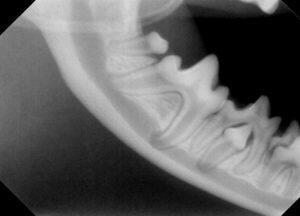

レントゲン検査では、

この様な感じです。

上顎永久犬歯は左右とも本当にありませんでした。